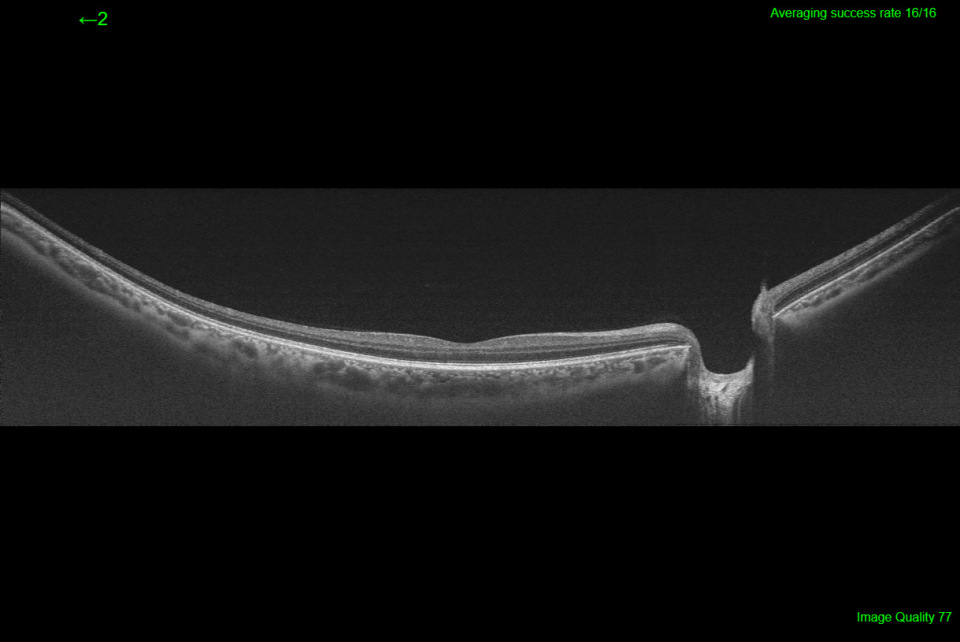

- Weitwinkel OCT & OCTA: Optional bis zu 21 mm – für umfassendere klinische Einblicke

- Kombinations-Scan: Verknüpft 3D-Volumendaten mit hochauflösenden Linearscans in einer einzigen Aufnahme

Das Swept-Source-OCT Triton bietet eine einzigartige Qualität in der Bildgebung des vorderen und hinteren Augenabschnitts. Mit einer beeindruckenden Brillanz sind die Strukturen von Glaskörper und Aderhaut gleichzeitig darstellbar. Dazu gibt es hochauflösende Fundusbilder, die Darstellung von Blutgefässen ohne Injektion von Kontrastmitteln und in der Variante Plus auch Fluoreszenz-Angiographie und Autofluoreszenz-Aufnahmen.